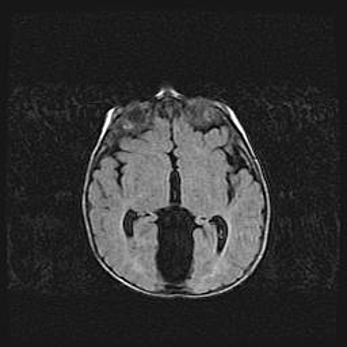

Сообщающаяся гидроцефалия. Кистозная энцефаломаляция головного мозга.

Возраст: 3 месяца 4 дня

Вес: 3100 г

Пол: женский

Окружность головы: 34 см

Срок гестации: 31 неделя

Кистозная энцефаломаляция головного мозга - одна из форм поражения головного мозга в детском возрасте. Характеризуется возникновением множественных и распространённых кист в коре, белом веществе и подкорковых образованиях головного мозга у плодов, новорождённых и детей раннего возраста. Развитие кистозной энцефаломаляции связано с внутриутробной асфиксией и гипотонией, родовой травмой, тромбозом синусов, пороками развития сосудов, инфекциями, сепсисом и другими причинами. Наиболее значимые инфекционные агенты: вирусы простого герпеса, цитомегалии, краснухи, токсоплазмы, энтеробактерии, золотистый стафилококк и другие.